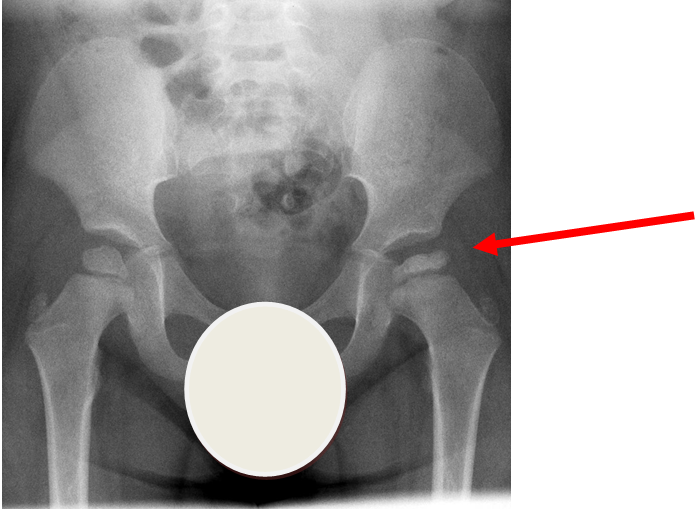

4. Slipped Upper Femoral Epiphysis (SUFE)

Subtle left sided SUFE.

Case courtesy of Dr Gagandeep Singh, Radiopaedia.org. From the case rID: 7688

Usually occurs in late childhood / adolescence and is more common in boys than girls (2:1).  It also presents more commonly in children whose weight is above the 90th centile.  Bilateral in 25% of cases.  Onset can be acute or subacute (ie children may present with >1day h/o pain or limp).  Children may walk with an antalgic gait out-toeing, with shortening of the affected limb.  If the slip is acute, the child may be unable to walk.  Diagnosis is made radiologically and frog-lateral views are required as it may be missed on AP views.  Urgent orthopaedic opinion is required.  Unstable slips can lead to avascular necrosis of the femoral head.

Investigation

• X-ray - AP pelvis with frog lateral view (must be discussed with ortho 1st on call / ED consultant if child <8 years old)